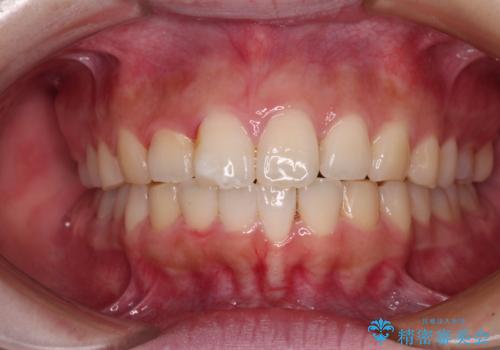

前歯のデコボコをインビザラインできれいに整える

- 前歯のデコボコと上下の隙間を気にして来院された患者様です。

前歯の捻れを改善するとともに、口元が少しでも引っ込むように治療計画を立て、仕上げることができました。